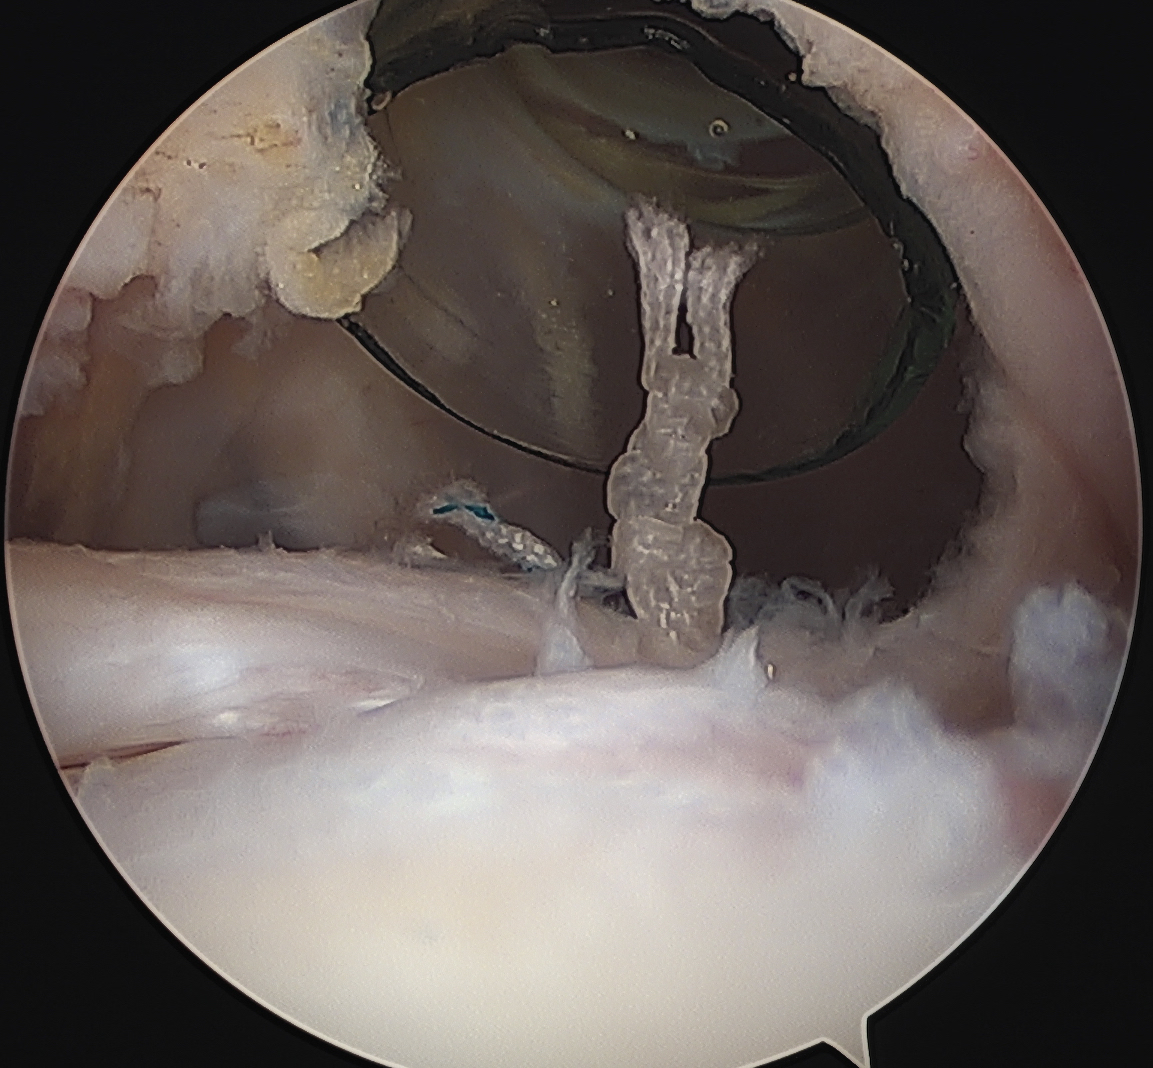

Comma sign

- medially retracted subscapularis tear

- exposes the superior insertion of superior glenohumeral ligament / coracohumeral ligament

Full thickness retracted subscapularis tear with comma sign

Full thickness completely retracted subscapularis, loss of rotator interval and comma sign

Full thickness completely retracted subscapularis, loss of rotator interval and comma sign